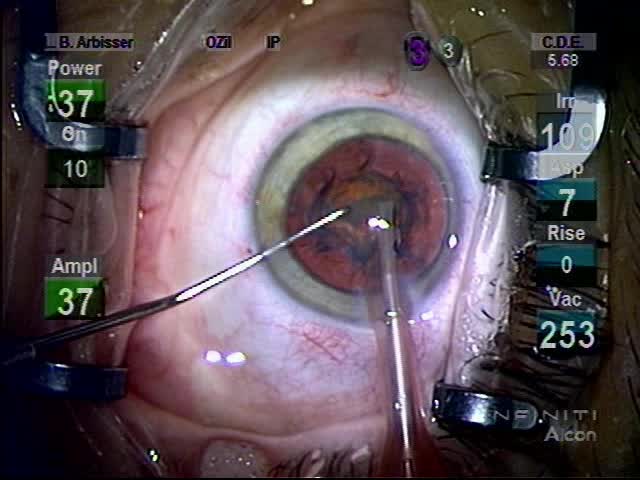

Intumescent Cataract

Lisa Brothers Arbisser, MD